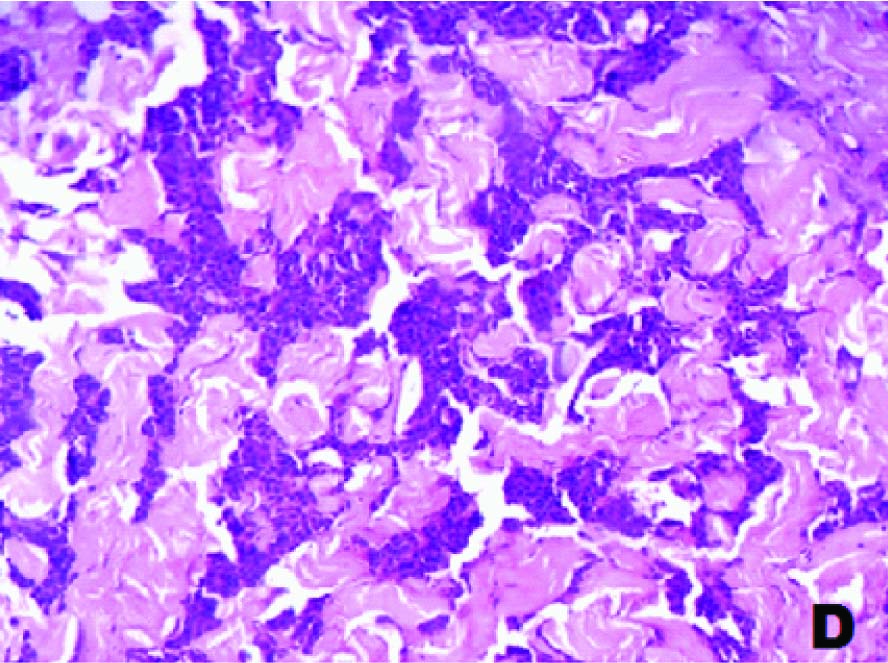

Sections from the abdominal skin nodules showed a subepithelial, infiltrating, malignant tumour with monomorphic cells arranged in sheets, nests, organoid, trabecular and mosaic patterns [Table/Fig-2c,2d]. They exhibited moderate degree of pleomorphism at places [Table/Fig-3a]. The cells had moderate to abundant granular cytoplasm and nuclei with salt and pepper type of chromatin [Table/Fig-3b]. The tumour cells were arranged in rosette- like fashion. Focal, large areas of necrosis were seen [Table/Fig-3c].

Section with monomorphic tumour cells in sheets (H&E,×400)

Section showing mosaic pattern and dense collagenous stroma in the tumour (H&E, ×100)